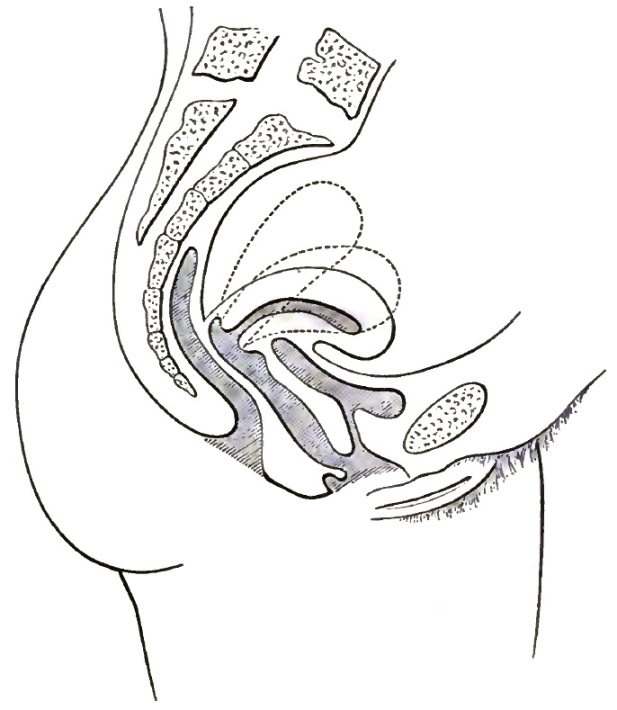

| 3. | FIRST DEGREE OF PROLAPSE OF THE POST-PARTUM UTERUS |

| 4. | SHOWING EXTREME DESCENT OF THE UTERUS AND OF THE PELVIC FLOOR, AND THE HERNIAL CHARACTER OF THE LESION |

| 5. | DESCENT OF THE VIRGIN UTERUS INTO THE VAGINAL CANAL, SHOWING THE REDUPLICATED VAGINAL WALLS |

| 6. | DESCENT OF THE UTERUS, SHOWING EXCESSIVE CIRCULAR ENLARGEMENT OF THE LACERATED CERVIX, CONSEQUENT UPON REDUPLICATION OF THE VAGINAL WALLS AND OUT-ROLLING OF INTRACERVICAL TISSUES |